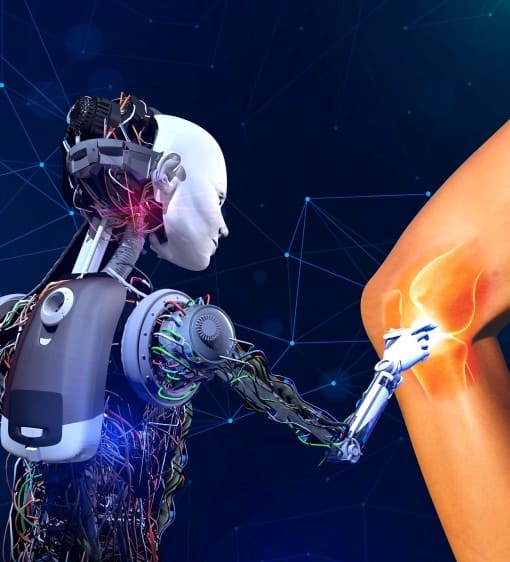

Robotic Knee Replacement Centre in Ahmedabad

Robotic Knee Replacement

robotic knee replacement surgery is the higher accuracy and ability to precisely plan the implant positioning to best fit the patient's anatomy.This allows for a highly personalized surgical experience and less pain during the recovery period.

Most Advanced healthcare Technology

Leverage advanced healthcare technology for the best outcomes.

With over 25 years of distinguished experience, Dr. Tejas Gandhi is a leading expert in orthopedics, renowned for his exceptional skills in joint replacement and orthopedic surgery. His extensive career encompasses a range of services including knee replacement, robotic knee replacement, microplasty (partial knee replacement), hip replacement, trauma care, and arthroscopy. Dr. Gandhi is particularly noted for his innovative use of robotic-assisted techniques and minimally invasive procedures that enhance patient outcomes and recovery.